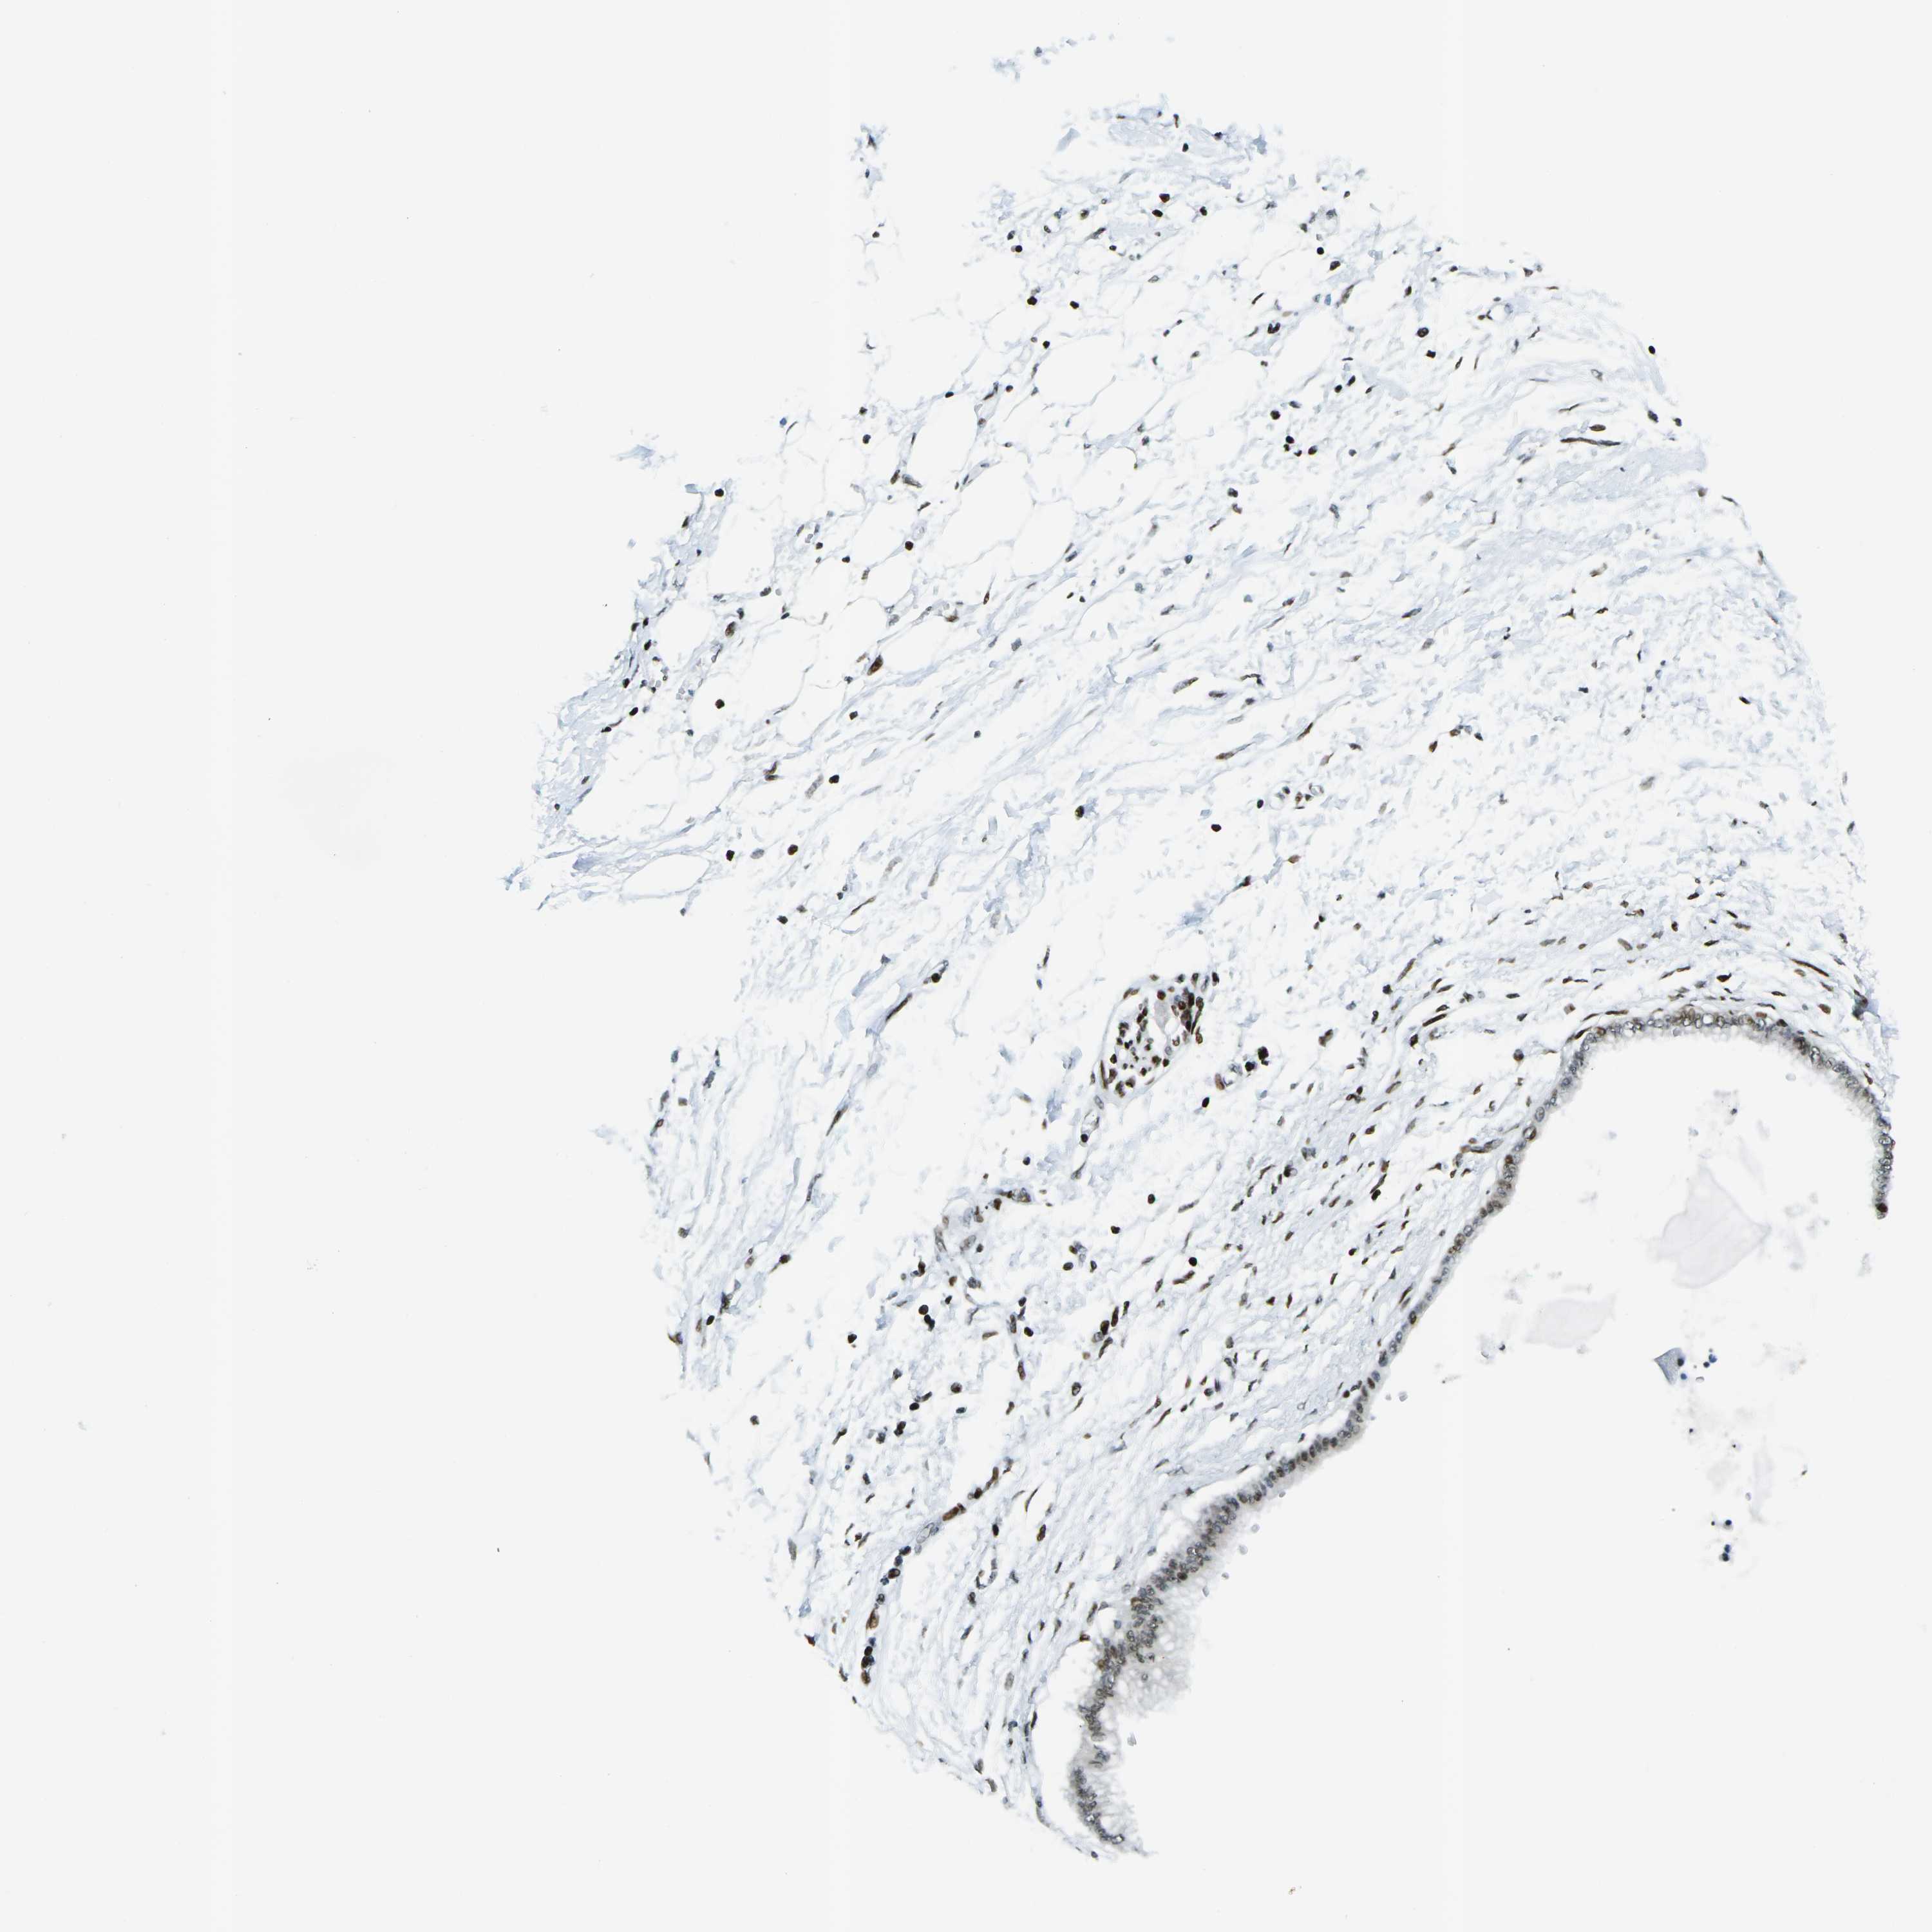

PANCREATIC CANCER - Protein expressioni

A mouse-over function shows sample information and annotation data. Click on an image to view it in a full screen mode. Samples can be filtered based on level of antibody staining by selecting one or several of the following categories: high, medium, low and not detected. The assay and annotation is described here.

Note that samples used for immunohistochemistry by the Human Protein Atlas do not correspond to samples in the TCGA dataset.

Antibody stainingi

Antibody staining in the annotated cell types in the current human tissue is reported as not detected, low, medium, or high, based on conventional immunohistochemistry profiling in selected tissues. This score is based on the combination of the staining intensity and fraction of stained cells.

Each image is clickable and will lead to virtual microscopy that enables deeper exploration of all samples and also displays staining intensity scores, fraction scores and subcellular localization as well as patient and tissue information for each sample.

Antibody HPA042570

Antibody CAB011481

Antibody CAB037178

Staining

High

Medium

Low

Not detected

Intensity

Strong

Moderate

Weak

Negative

Quantity

>75%

75%-25%

<25%

None

Location

Nuclear

Cytoplasmic/membranous

Cytoplasmic/membranous,nuclear

Adenocarcinoma, NOS

Adenocarcinoma, metastatic, NOS